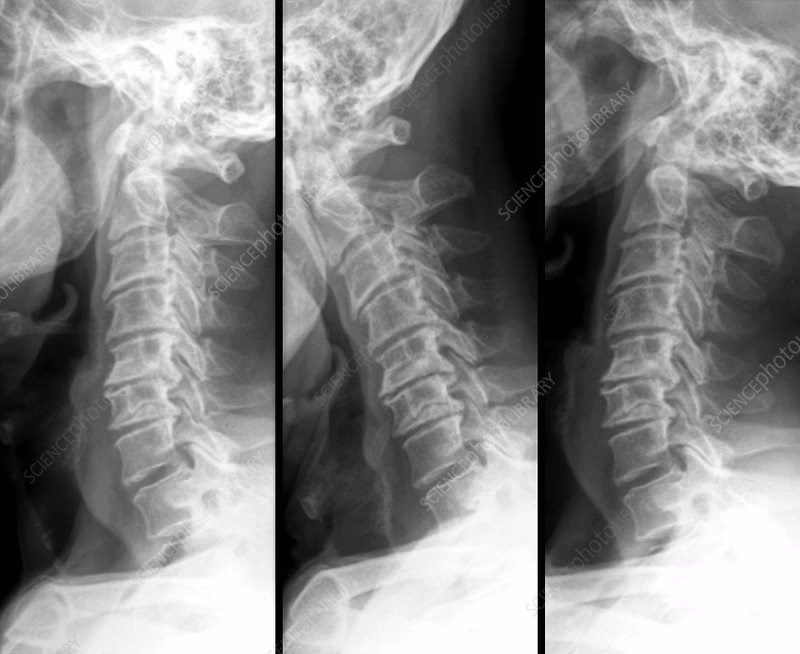

Konventionel Røntgen (CR)

Konventionel røntgen er det absolut vigtigste og mest anvendte værktøj til screening. Det er en hurtig, billig og let tilgængelig undersøgelse, der giver fremragende information om knoglernes position i forhold til hinanden. Røntgenbilleder, ofte taget med nakken bøjet forover (fleksion) og bagover (ekstension), kan afsløre instabilitet som AAS. Lægen måler afstanden mellem specifikke knoglepunkter for at vurdere, om der er en unormal forskydning. Selvom røntgen er guldstandarden for screening, har metoden sine begrænsninger: den kan ikke visualisere bløddele som ledhinder, rygmarv eller nerverødder.